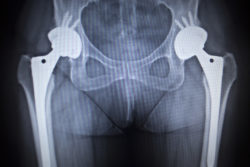

According to the lawsuit, when the patient was 68-years-old, she was implanted with the DePuy ASR hip prosthetic on her right side. This surgery took place at Duke University Medical Center in Durham, N.C. The plaintiff alleges that the prosthesis caused innumerable medical issues including difficulty with walking, chronic pain and inflammation.

The ASR hip implant was removed from the plaintiff in May 2017. This surgery involved complete removal and replacement with another prosthetic. According to the original MDL, those who have to have the hip implant removed often experience bone loss and leg length discrepancies as well as take on risks associated with total hip arthroscopy such as dangerous blood clots.